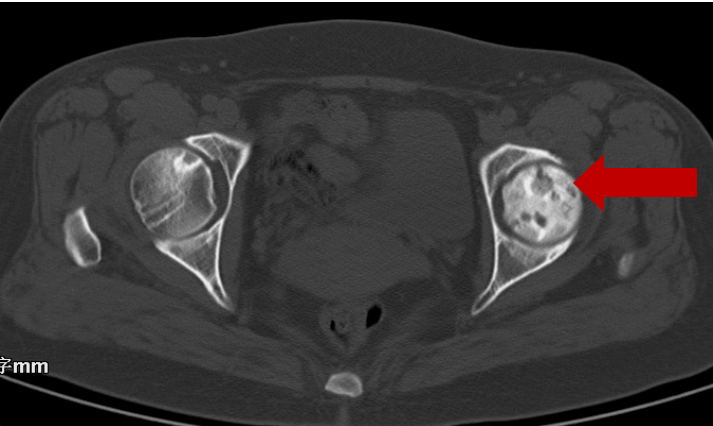

2021年05月20日末次复查CT显示:

右股骨头坏死三期,左股骨头正常

周先生此人,年龄为52岁,在2008年12月的时候,被明确诊断成了“右侧股骨头缺血性坏死”,属于二期病变,外院给出了“人工关节置换术”的建议,然而患者拒绝了。在2008 - 12 - 12这一天,首次于我院进行介入手术治疗,之后又间断进行介入手术治疗9次,末次复查时间是2021 - 05 - 20日,显示右侧股骨头坏死达到三期,左侧股骨头是正常的。在2024年3月,对周先生进行电话随访,他自述病程已经超过15年,除了介入治疗之外,并没有进行关节置换手术。如今,他身体不存在特别的不舒服状况,极为感激徐州市中医院介入科的高超诊疗技艺,致使他重新获得健康,得以正常地生活 。